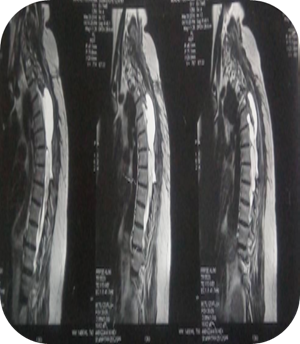

Vertebro-Medullary Hydatid Cyst Case Report Diagnostic and Therapeutic Approach